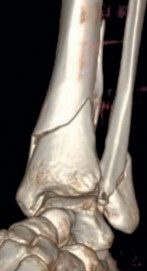

Fig 2.2-3a–h A CT scan with 3D reconstruction.

a–d Sagittal (a–b), coronal (c), and axial (d) images demonstrate displaced posterior, anterolateral, and medial fracture fragments resulting in intraarticular step and gap. The incongruent tibiotalar joint is best appreciated on the sagittal scan.

e–h The 3D reconstructed images show the external fracture anatomy and general alignment.